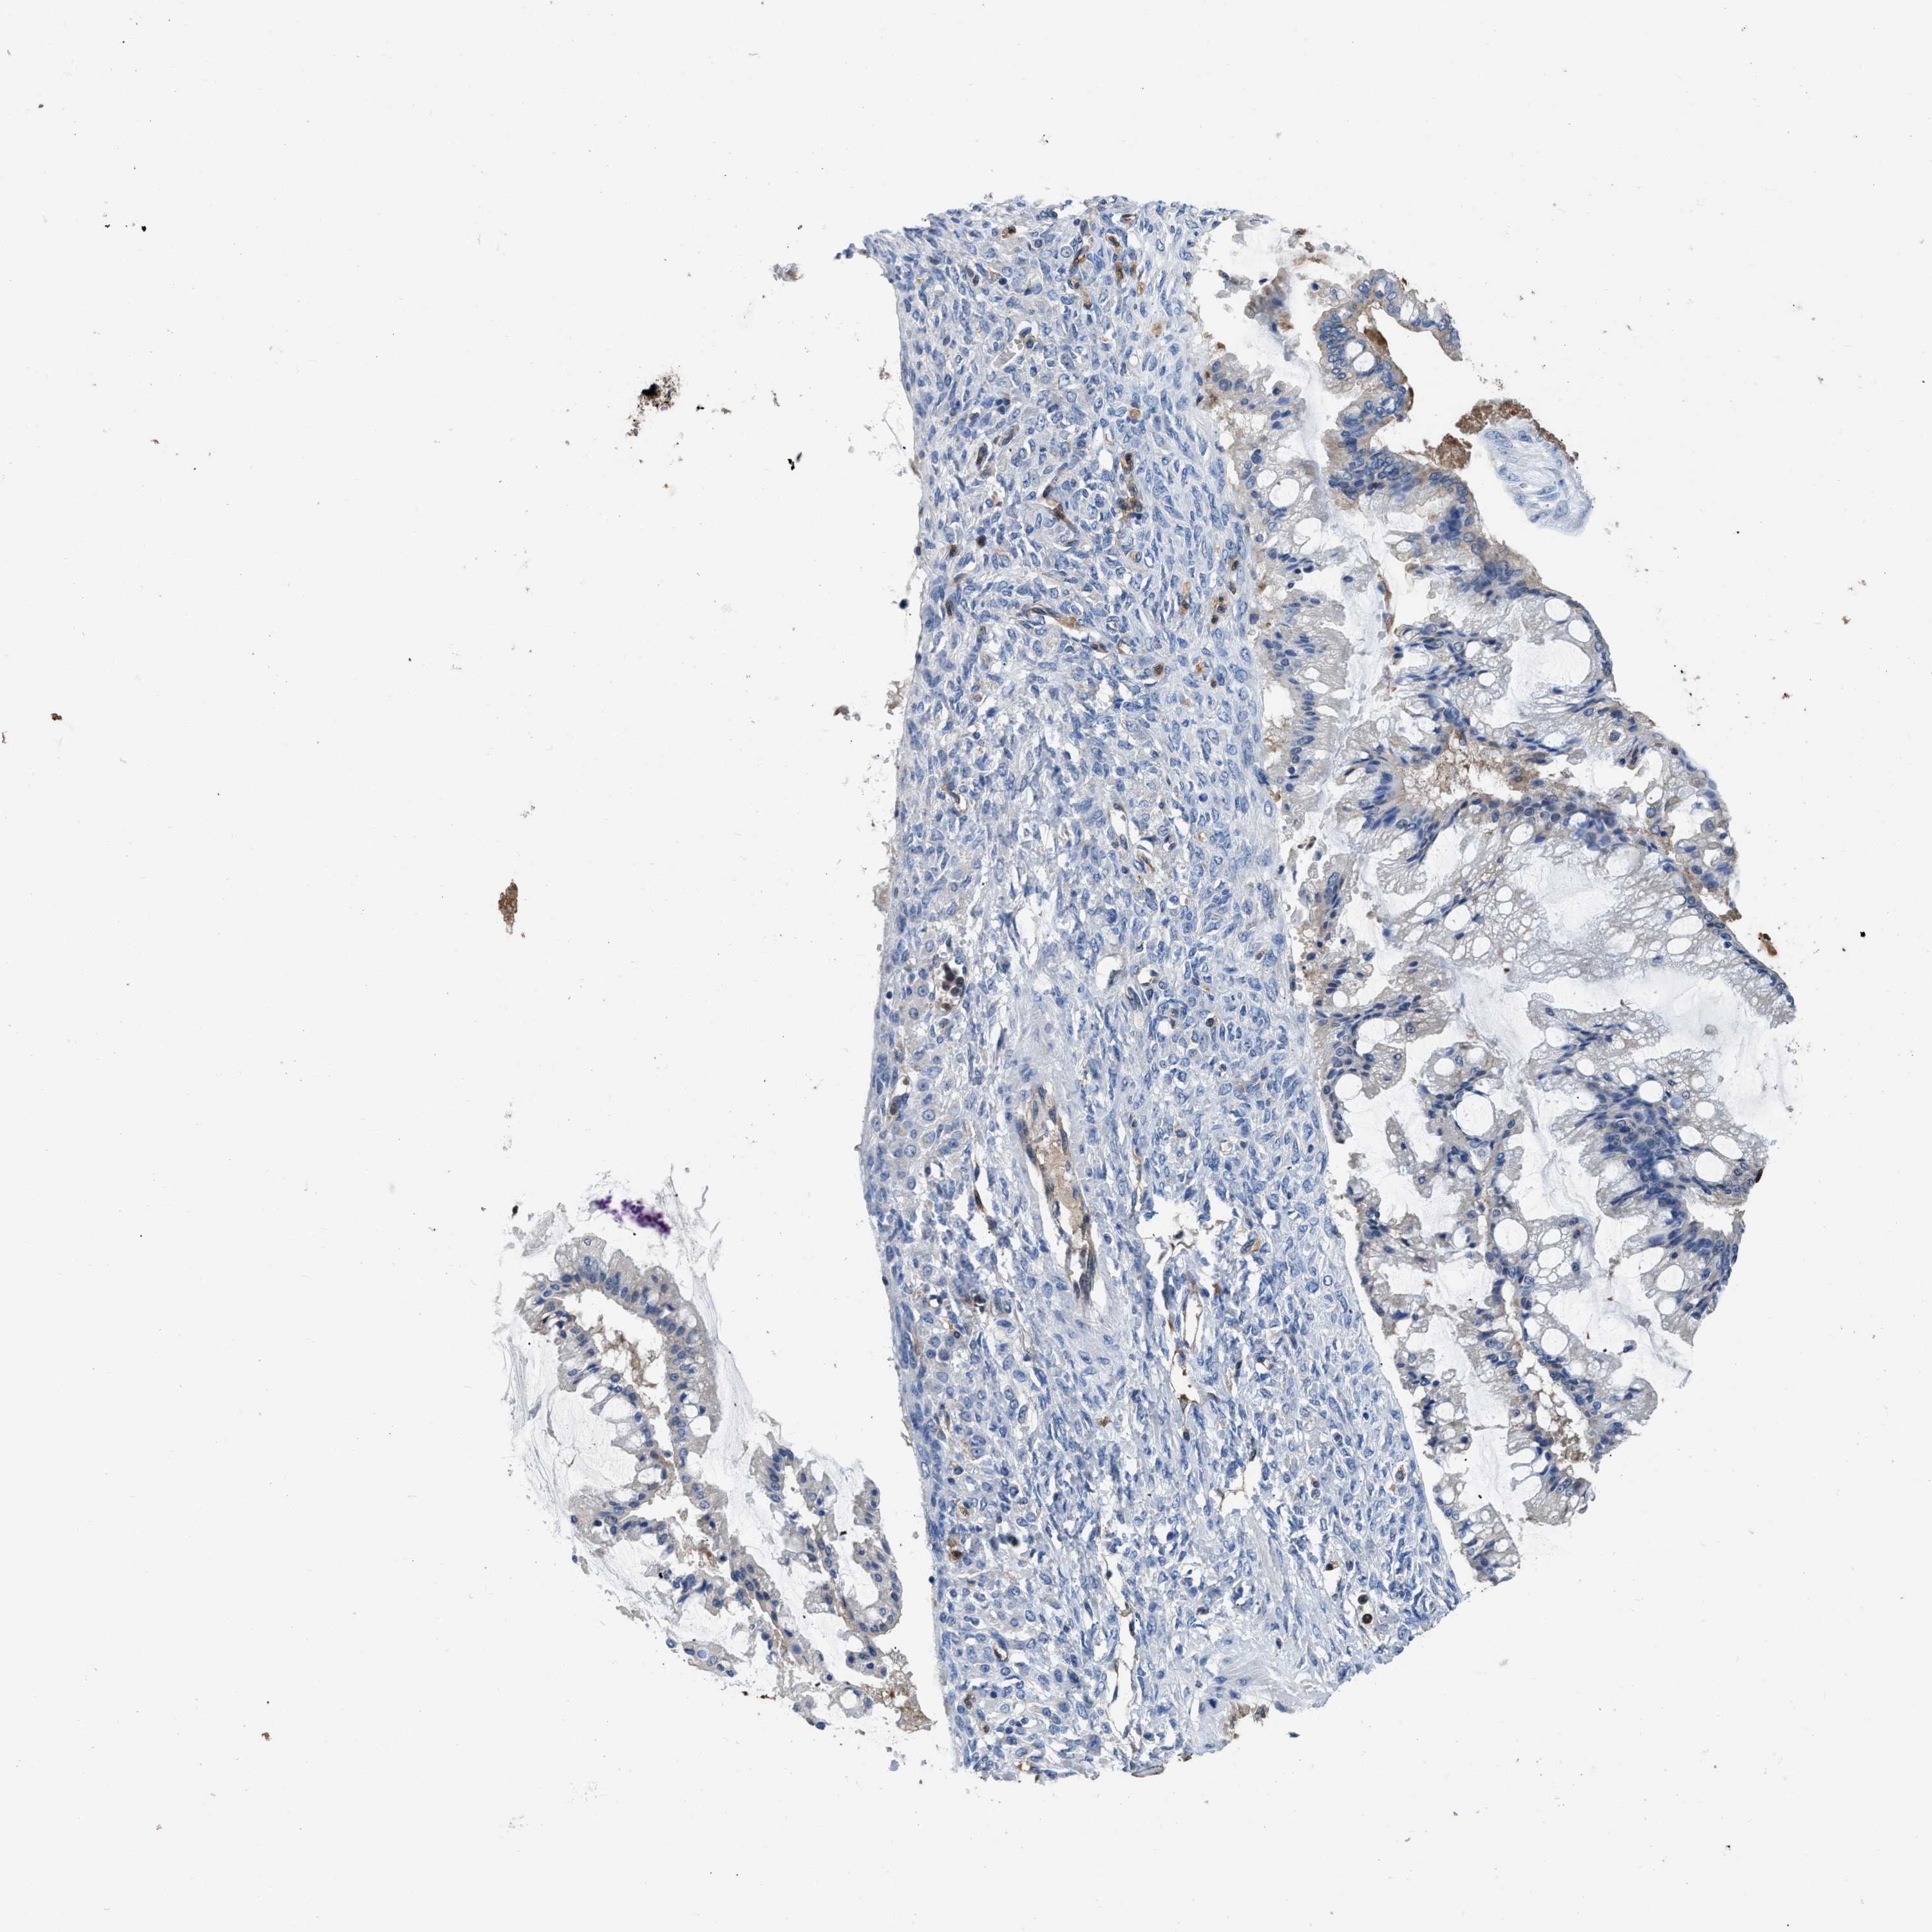

OVARIAN CANCER - Protein expressioni

A mouse-over function shows sample information and annotation data. Click on an image to view it in a full screen mode. Samples can be filtered based on level of antibody staining by selecting one or several of the following categories: high, medium, low and not detected. The assay and annotation is described here.

Note that samples used for immunohistochemistry by the Human Protein Atlas do not correspond to samples in the TCGA dataset.

Antibody stainingi

Antibody staining in the annotated cell types in the current human tissue is reported as not detected, low, medium, or high, based on conventional immunohistochemistry profiling in selected tissues. This score is based on the combination of the staining intensity and fraction of stained cells.

Each image is clickable and will lead to virtual microscopy that enables deeper exploration of all samples and also displays staining intensity scores, fraction scores and subcellular localization as well as patient and tissue information for each sample.

Antibody HPA029501

Antibody CAB019421

Cystadenocarcinoma, serous, NOS

Carcinoma, endometroid

Cystadenocarcinoma, mucinous, NOS

Carcinoma, NOS